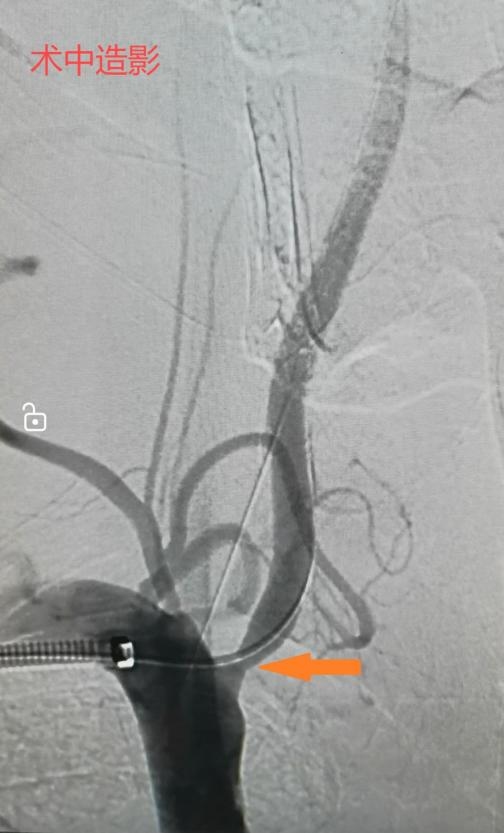

桂林医院血管外科舒畅教授团队经过仔细评估,决定采用微创腔内治疗,植入椎动脉支架进行治疗。右侧椎动脉微创血管重建手术具有创伤小、恢复快、效果显著等优点,是治疗血管狭窄的常用手段之一。

手术过程中,血管外科执行主任李鑫使用如头发丝粗细的导丝迅速通过病变段狭窄建立治疗轨道,沿着这根轨道将一枚精细的血管支架精准无误地放置在病变部位的血管,使得之前闭塞了80%的管腔恢复到了正常的血液供应水平。整个手术过程不到半小时,而唯一的“创伤”就是右手肘部的一个小小针眼。术后,王大叔的头晕、头疼及黑矇等症状均得到了明显缓解,生活质量得到了显著提高。